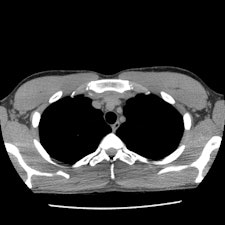

When performing CT on trauma patients, the radiology department at the Medical University of Graz starts with an unenhanced head CT, followed by a bolus tracking guided arterial phase acquisition covering the region from the Circle of Willis to the renal arteries. This CT scan can be used to assess the chest, vessel, and spine of the patient. Sorantin suggests that it be followed by a late-phase abdominal and pelvic scan. A pediatric radiologist should be present to immediately view the images and make decisions with respect to what additional exams are needed.